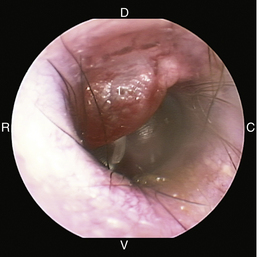

image

Figure 20-2 Normal anatomy of the canine tympanic membrane of the right ear. 1, Pars flaccida; 2, pars tensa; 3, stria mallearis; C, caudal; D, dorsal; R, rostral; V, ventral.

(Courtesy of Dr. Lynette Cole, The Ohio State University, Columbus, Ohio.)

Figure 20-8 Normal canine tympanic membrane of the left ear. 1, Pars flaccida; 2, pars tensa; 3, stria mallearis; 4, bulla septum; C, caudal; D, dorsal; R, rostral; V, ventral.